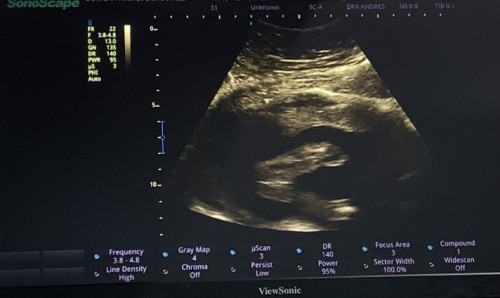

Baby Girl! 🤍

Hello mga sis. Nagpa ultrasound ako kahapon 19w3d at ang sabi ni doctora baby girl daw. Sobrang saya ko 🥰 Sa tingin niyo po ba girl talaga? Excited kasi ako mamili ng gamit hehe. Pero natatakot ako baka magkamali parang nakatalikod kasi si baby kahapon at naka breech din siya.